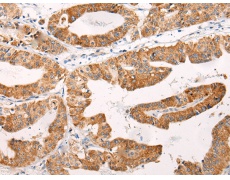

IHC positive control: |

Human prostate cancer and Human brain |

IHC Recommend dilution: |

40-200 |